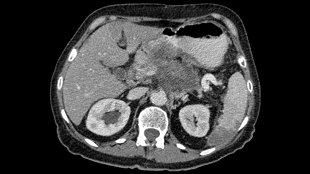

胰腺癌,圖片來(lái)自維基共享資源|Hekkerhoff